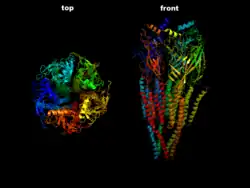

The nicotinic acetylcholine receptor

The nicotinic acetylcholine receptor

MG is an autoimmune synaptopathy. The disorder occurs when the immune system malfunctions and generates antibodies that attack the body's tissues. The antibodies in MG attack a normal human protein, the nicotinic acetylcholine receptor, or a related protein called MuSK a muscle-specific kinase.[19] Other less frequent antibodies are found against LRP4, Agrin and titin proteins.[20][21]

Myasthenia gravis is an autoimmune disease which results from antibodies that block or destroy nicotinic acetylcholine receptors at the junction between the nerve and muscle.[1] This prevents nerve impulses from triggering muscle contractions.[1] Some medicines may worsen the weakness.[5] Rarely, an inherited genetic defect in the neuromuscular junction results in a similar condition known as congenital myasthenia.[6][7] Babies of mothers with myasthenia may have symptoms during their first few months of life, known as neonatal myasthenia.[1] Diagnosis can be supported by blood tests for specific antibodies, the edrophonium test, or a nerve conduction study.[1]

Immunomodulating substances, such as drugs that prevent acetylcholine receptor modulation by the immune system, are currently being researched.[59] Some research recently has been on anti-c5 inhibitors for treatment research as they are safe and used in the treatment of other diseases.[60] Ephedrine seems to benefit some people more than other medications, but it has not been properly studied as of 2014.[7][61] In the laboratory MG is mostly studied in model organisms, such as rodents. In addition, in 2015, scientists developed an in vitro functional all-human, neuromuscular junction assay from human embryonic stem cells and somatic-muscle stem cells. After the addition of pathogenic antibodies against the acetylcholine receptor and activation of the complement system, the neuromuscular co-culture shows symptoms such as weaker muscle contractions.[62]